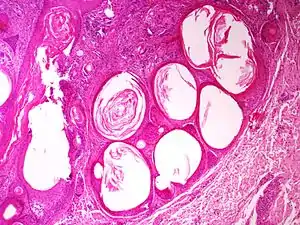

Trichoadenoma

A trichoadenoma is a cutaneous condition characterized by a solitary, rapidly growing skin lesion ranging from 3 to 15mm in diameter.[2]:675